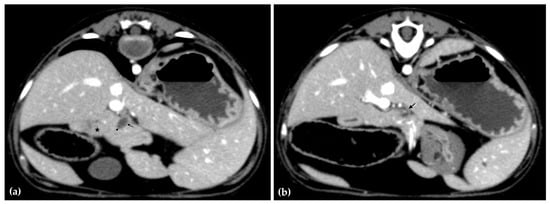

On histopathology, portal regions were variably closely apposed (up to two portal regions in a single high power (0.237 mm2) field) (Figure 6a). Throughout the sections of liver examined, biliary profiles were often absent or markedly decreased in size in portal regions. Occasionally, especially in areas adjacent to the gallbladder, there were increased numbers of biliary profiles in portal regions (biliary hyperplasia) (Figure 6b). Randomly scattered throughout the liver there were foci of lytic hepatocellular necrosis with an infiltrate of primarily neutrophils and fewer eosinophils (Figure 6c). Small to moderate numbers of eosinophils and neutrophils also multifocally infiltrated portal regions. The epithelium lining the cystic bile duct was variably attenuated. The wall of the cystic bile duct at the region of stenosis noted grossly was expanded by a proliferation of fibrous connective tissue with plump, reactive fibroblasts in a myxomatous matrix (fibroplasia) (Figure 6d). The sections of common bile duct examined were within normal limits. There was no evidence of either copper accumulation or bile stasis in the sections of liver stained with rhodanine and Hall’s special stains.

Figure 6.

H&E stain. Example of three portal regions (black arrows) which are closely apposed and lack biliary profiles (a). Example of a portal region with biliary hyperplasia. Individual biliary profile pointed out with a black arrow and magnified inset (b). Example of multifocal, random hepatocellular necrosis (black arrows) (c). Stenotic bile duct. The wall is thickened by reactive fibroblasts and eosinophilic to lightly basophilic stroma (fibroplasia and fibrosis; black bracket and magnified inset). The lumen of the duct is marked with a black asterisk (d).

Postmortem histopathologic examination of the cystic bile duct revealed fibrosis and fibroplasia of the wall leading to regionally extensive stenosis (Figure 5 and Figure 6d). This finding is suspected to have contributed to the clinical evidence of biliary obstruction. The lack of significant inflammation may be suggestive of a congenital biliary malformation rather than a secondary reactive change to inflammatory biliary disease. Portal regions in some areas of the liver were closely apposed and lacked biliary profiles which may also be supportive of a congenital anomaly (Figure 6a). With closely apposed portal regions, ductal plate malformation and congenital hepatic fibrosis were considered; however, the lack of significant periportal or bridging fibrosis, absence of portal vein hypoplasia, and absence of irregular or cystic ductal structures in this case make these less likely. Nonetheless, a mild or early form of this condition cannot be ruled out [19].

Other potential causes of stenosis such as a chronic, resolved inflammatory process (such as previous parasitic migration) or trauma cannot be definitively ruled out. There was no evidence of infectious organisms (bacteria, parasitic or fungal elements, or viral inclusions) in the sections of liver or biliary duct examined histologically. However, as light microscopy is often an insensitive method for identifying infectious agents, they cannot be fully ruled out using histology alone. Testing for infectious organisms (such as serology and PCR) without any clinical antemortem or postmortem evidence of infectious disease would be extremely challenging without clues of what to test for; finances were also limited. Culture of liver and bile, or bile duct tissue was not pursued but may have helped to rule out a fungal or bacterial etiology but may not directly relate to these lesions. No specific cause for the multifocal random hepatocellular necrosis was identified (Figure 6c). Considerations included acute sepsis or viral infection; however, no source of sepsis or clinical signs related to sepsis were identified. Moreover, the young age of the bear and lack of systemic signs of chronic inflammation along with lack of significant associated inflammation in the stenotic region further strengthen the suspicion for a congenital structural defect [20].